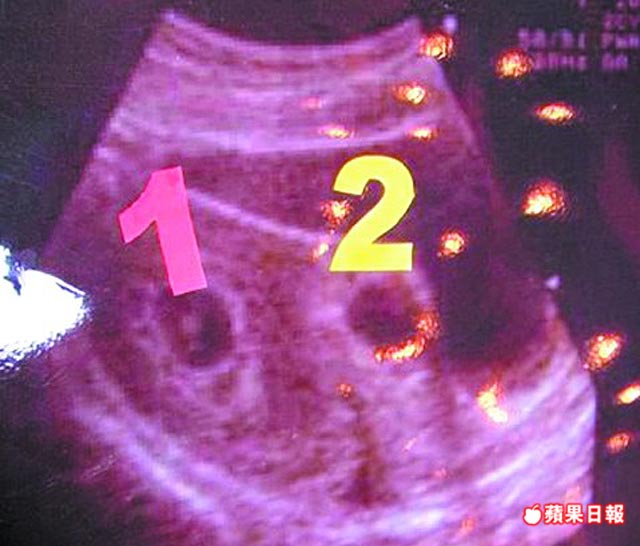

子宮鏡取胚胎 長庚創首例 婦產科醫師蔡鋒博表示,這名31歲婦人,經人工受孕懷雙胞胎,但妊娠第6周時,發現有一個胚胎不當著床於剖腹產傷口上,因此轉診       字級: ...